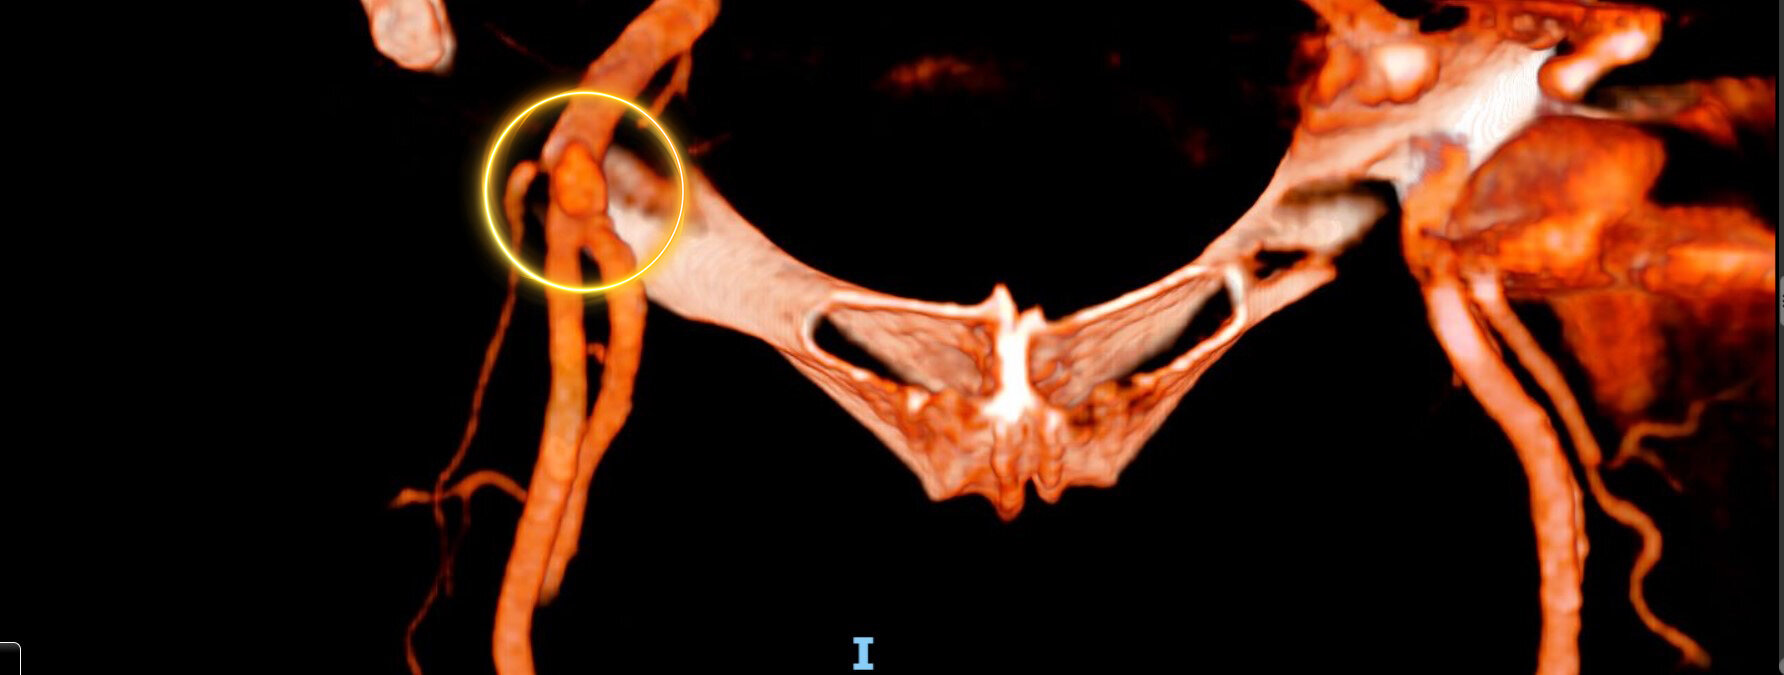

Gli pseudoaneurismi iliaci si associano spesso a interventi chirurgici ricostruttivi come il bypass aorto-iliaco e, più raramente, possono essere conseguenza di un trauma pelvico.